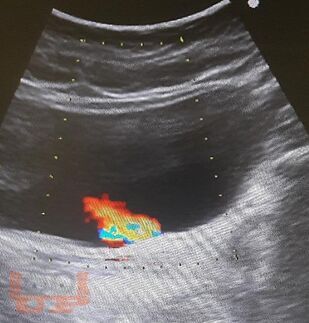

Пособие содержит материал, отражающий современные данные о лечебно-диагностических концепциях основных врождённых и приобретённых урологических заболеваниях взрослых и детей. В пособии раскрыты ключевые позиции, этиологии, патогенеза, классификации, клинических проявлений, диагностики, консервативного и хирургического лечения, возможных осложнений и исходов урологических заболеваний. Сделан акцент на эмбриопатогенез и пренатальную диагностику врождённых аномалий развития органов мочевыводящей системы у детей. Пособие содержит перечень вопросов для самоконтроля, тестовые задания и ситуационные задачи.